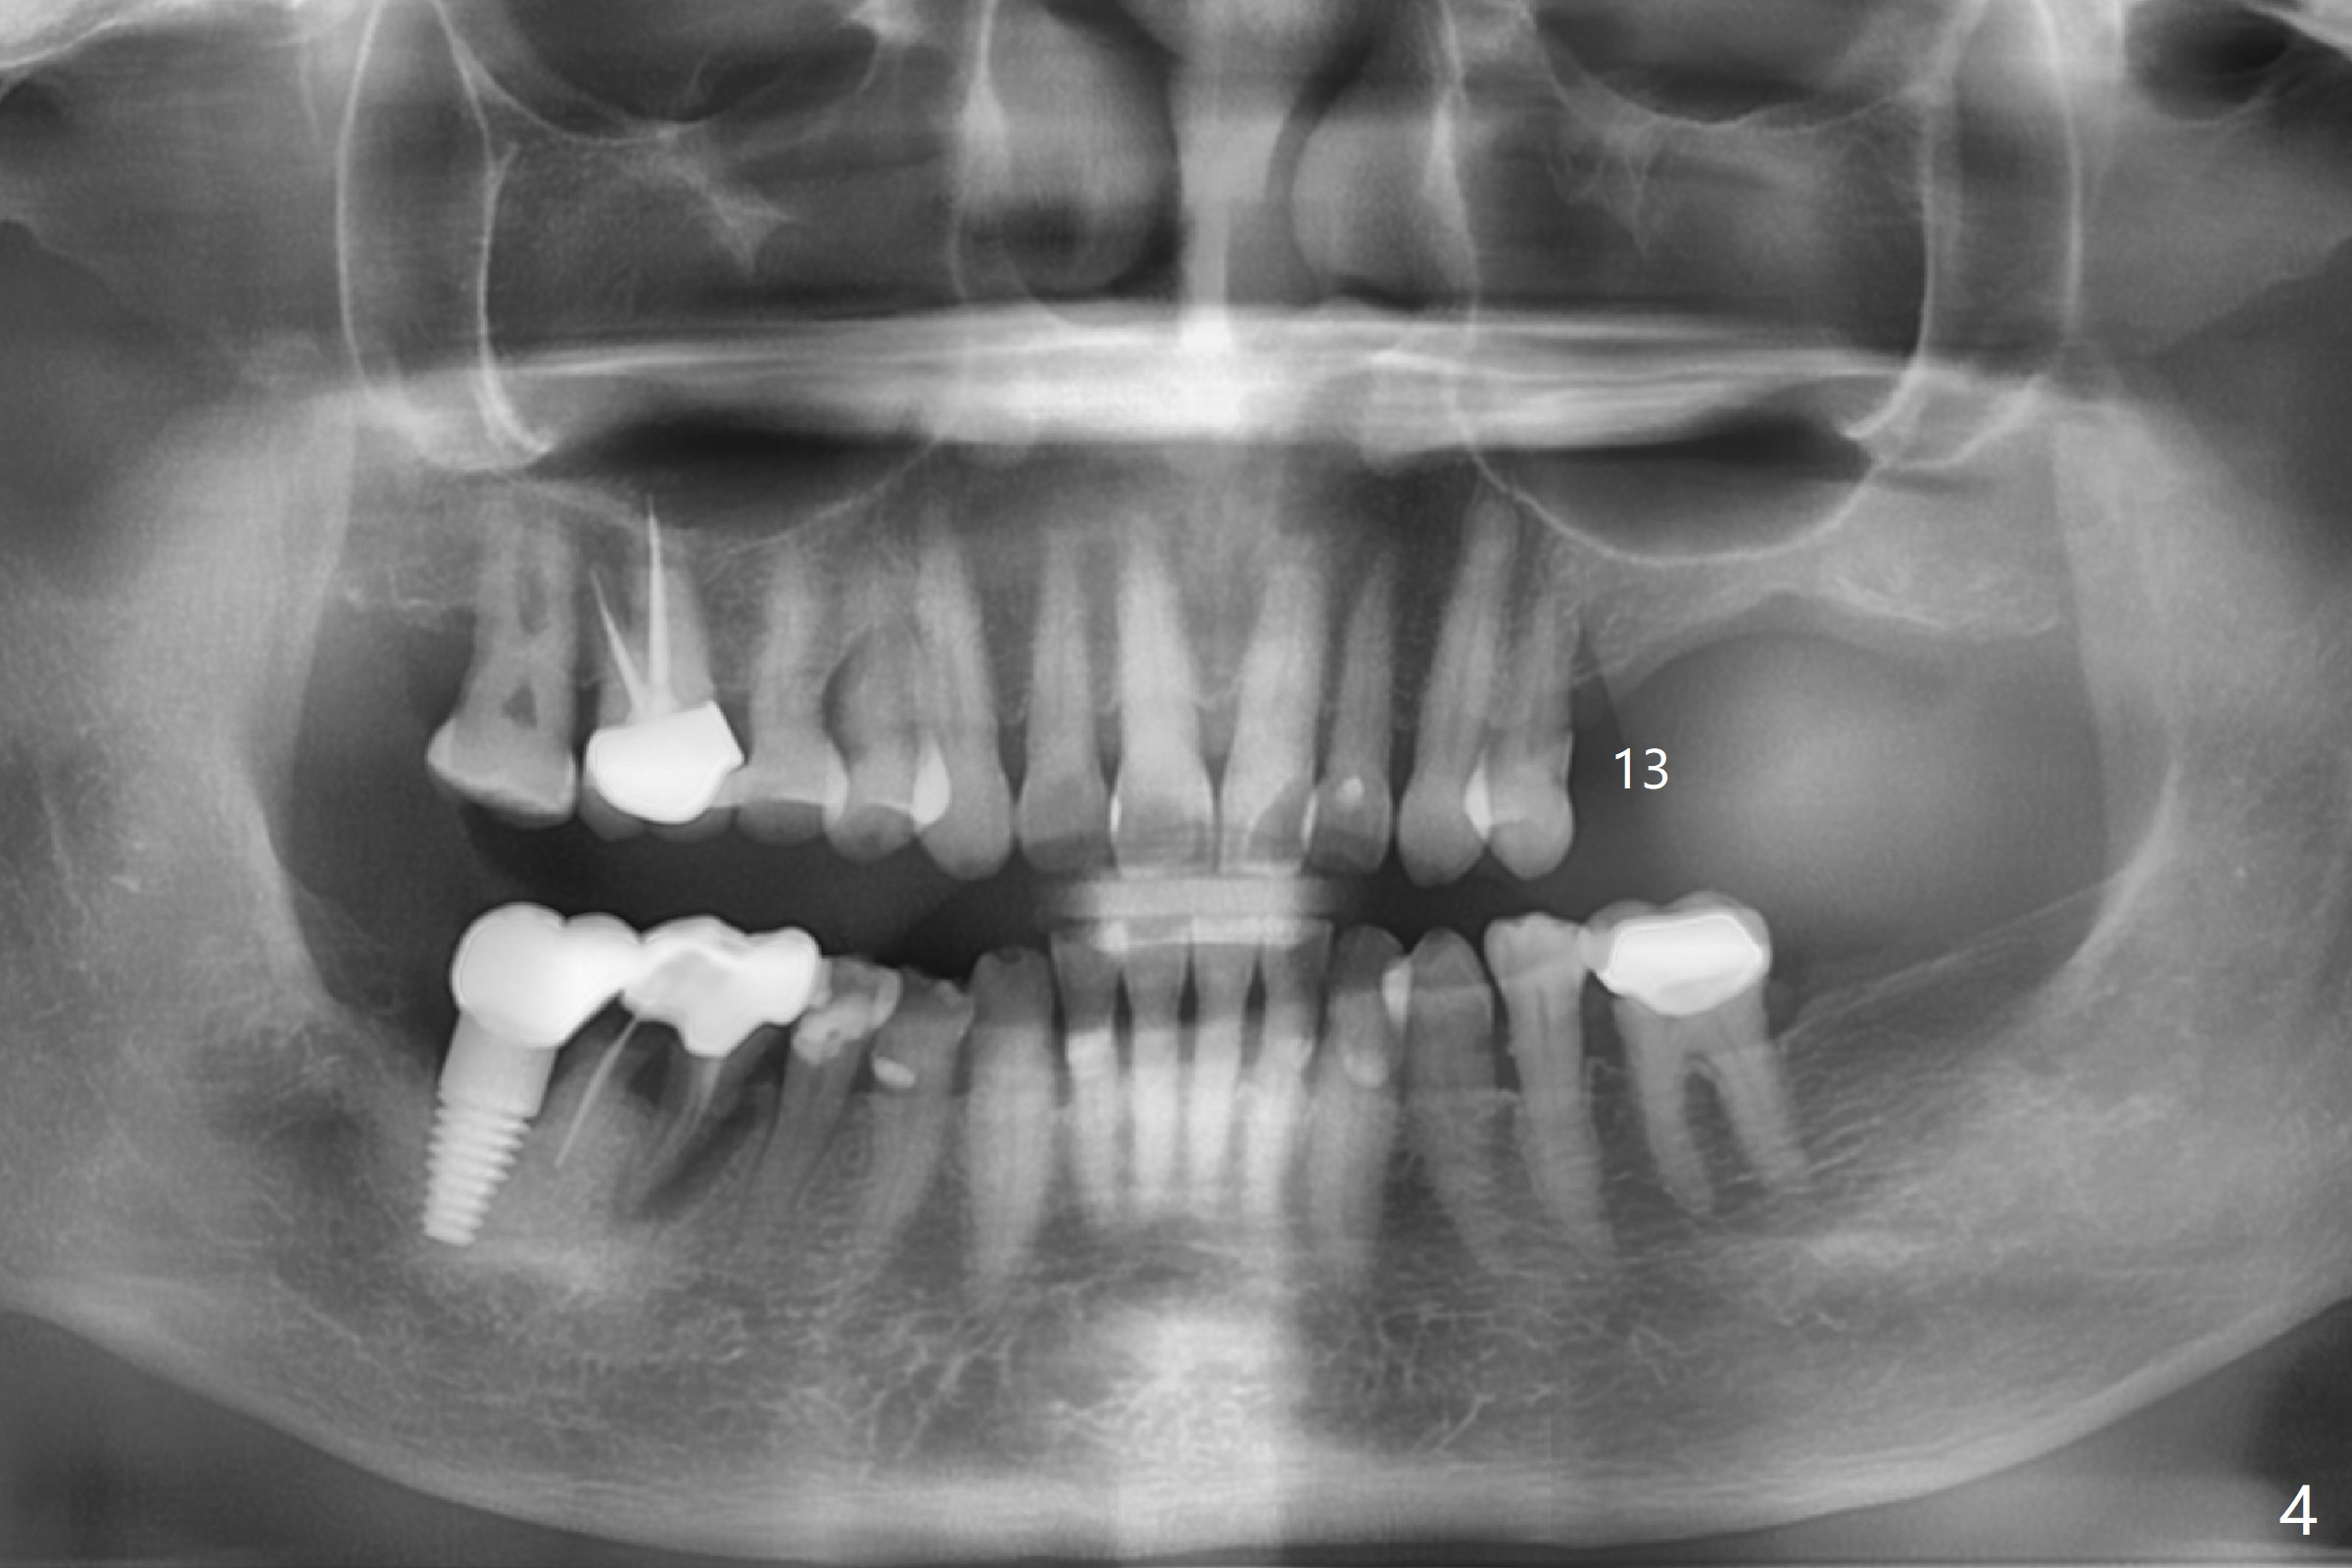

A 67-year-old woman masticates on the right side (Fig.1 (5 years post #30 RCT), as compared to Fig.4,6). One year and 6 months later, there is a fistula mesiobuccal to the tooth #30 (Fig.2 >,4) with mesial root fracture (Fig.3 >). Impression is taken for guide; a 5x11.5 mm implant will be placed slightly distal and lingual to the center of the septum (Fig.5).